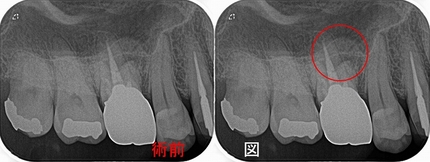

そこから、1年後

病変は殆ど無くなってきています

(他の歯科医院で治療をした際に仮歯を外したそうなんですが、縁下ににセメントが・・・)

ただ、9月から違和感というか痛みがでてきているそうで、温かい物冷たいもので痛みが出るそう。

先生も患者さんもこの歯を疑っているようなんですが・・・